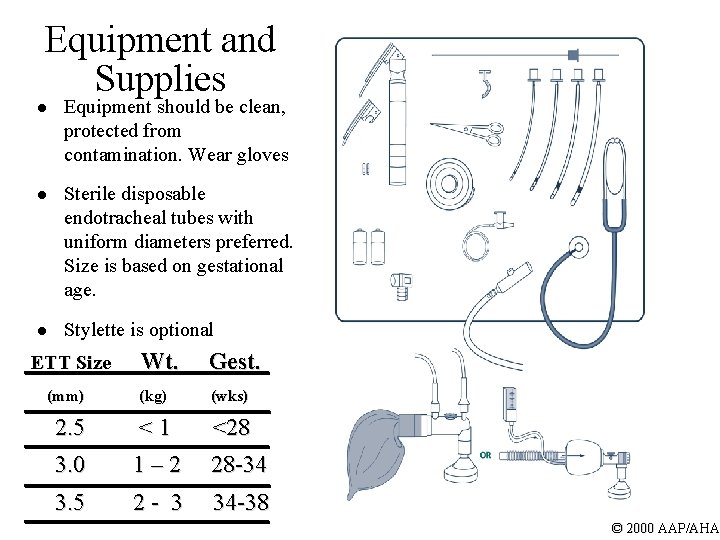

Equipment and Supplies l Equipment should be clean, protected from contamination. Wear gloves l Sterile disposable endotracheal tubes with uniform diameters preferred. Size is based on gestational age. l Stylette is optional ETT Size (mm) Wt. Gest. (kg) (wks) 2. 5 < 1 <28 3. 0 1 – 2 28 -34 3. 5 2 - 3 34 -38 © 2000 AAP/AHA